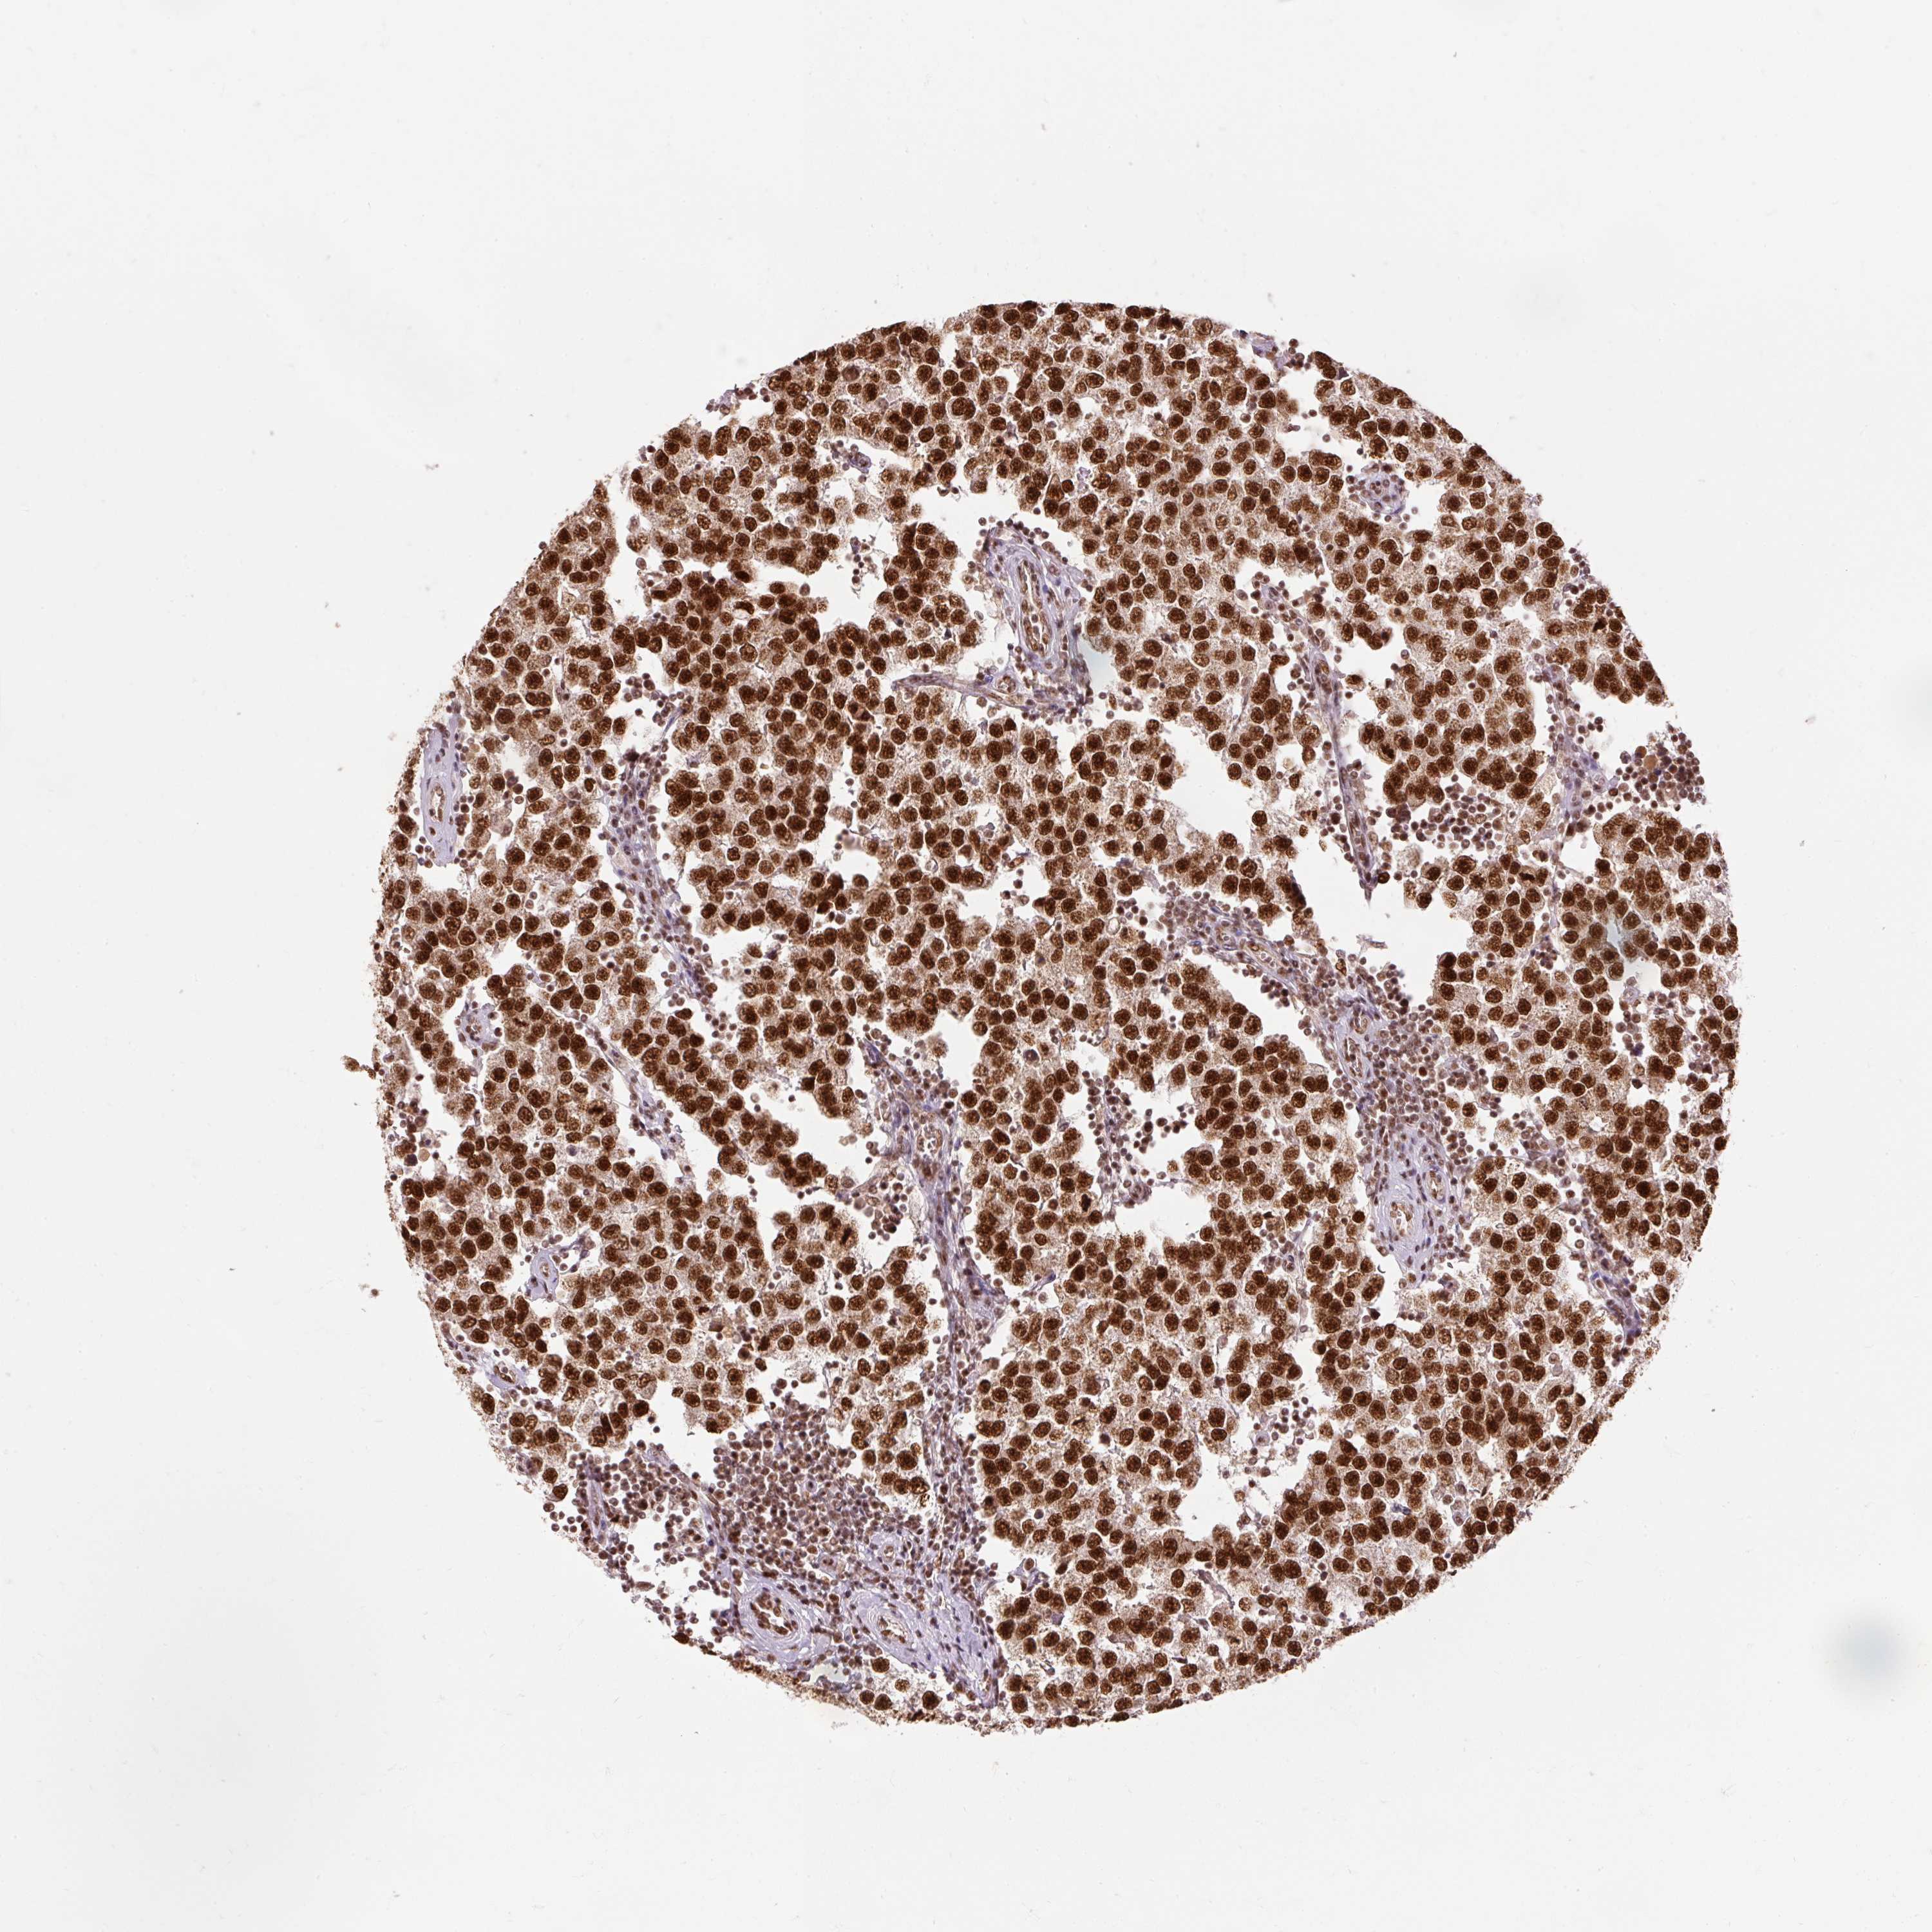

TESTIS CANCER - Protein expressioni

A mouse-over function shows sample information and annotation data. Click on an image to view it in a full screen mode. Samples can be filtered based on level of antibody staining by selecting one or several of the following categories: high, medium, low and not detected. The assay and annotation is described here.

Note that samples used for immunohistochemistry by the Human Protein Atlas do not correspond to samples in the TCGA dataset.

Antibody stainingi

Antibody staining in the annotated cell types in the current human tissue is reported as not detected, low, medium, or high, based on conventional immunohistochemistry profiling in selected tissues. This score is based on the combination of the staining intensity and fraction of stained cells.

Each image is clickable and will lead to virtual microscopy that enables deeper exploration of all samples and also displays staining intensity scores, fraction scores and subcellular localization as well as patient and tissue information for each sample.

Antibody HPA052589

Seminoma, NOS

Carcinoma, Embryonal, NOS